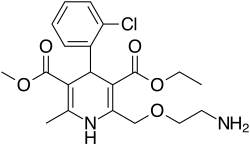

| Formula | C20H25ClN2O5 |

| Molar mass | 408.88 g·mol−1 |

| Chirality | Racemic mixture |